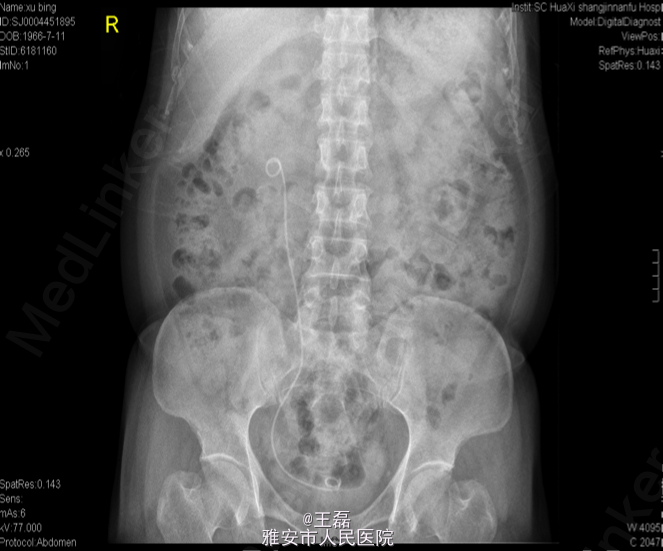

术前KUB:右肾结石:1.0*0.9cm